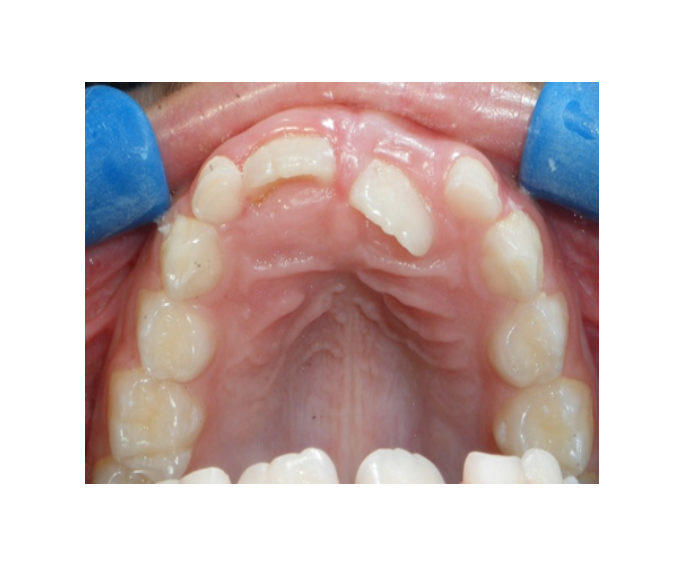

Clase I Protrusión

dental